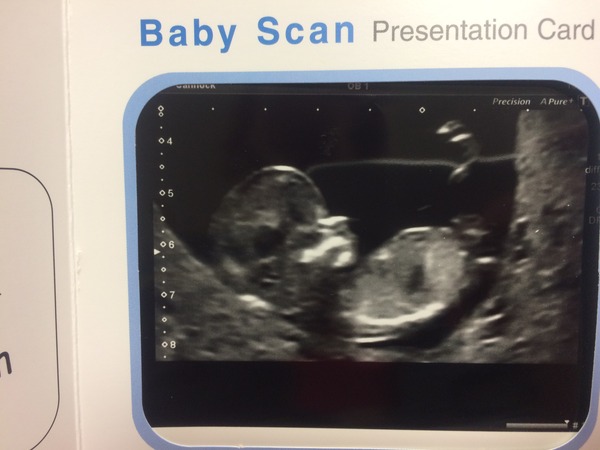

crazypuglady · 07/04/2015 19:51

Scan was incredible. Date changed by one day so I'm now 12+6 and due on 14th Oct. Baby was incredible wiggly and kept waving a foot at us! Pic is pretty good Grin

Yay! Congratulations crazypuglady on that lovely picture of your little one :)

Gorgeous crazypug!!